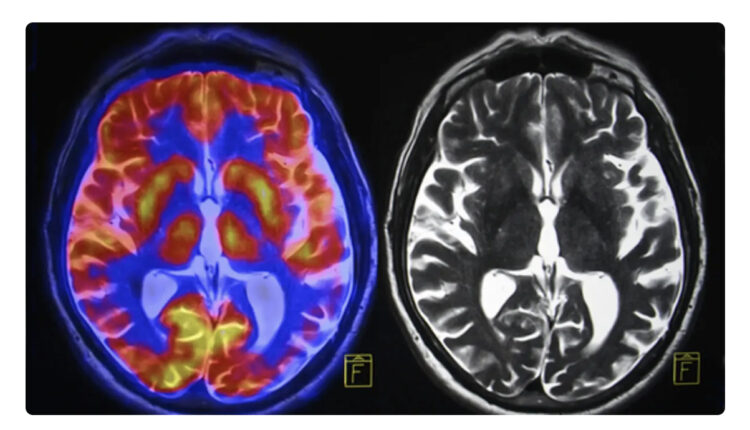

تتعدى تأثيرات وباء كورونا الآثار الاقتصادية والصحية، فقد كشف بحث جديد أن أدمغة المراهقين الذين عايشوا عمليات الإغلاق المرتبطة بالفيروس ظهر عليهم علامات الشيخوخة المبكرة.

وقارن الباحثون فحوصات التصوير بالرنين المغناطيسي لـ 81 مراهقاً في الولايات المتحدة قبل الوباء، بين نوفمبر 2016 ونوفمبر 2019، مع 82 مراهقاً تم جمعهم بين أكتوبر 2020 ومارس 2022، أثناء الوباء ولكن بعد رفع الإغلاق، بحسب صحيفة “غارديان” البريطانية.

تغيرات في الدماغ

وبعد مطابقة 64 مشاركاً في كل مجموعة لعوامل تشمل العمر والجنس، وجد الفريق أن التغيرات الجسدية في الدماغ التي حدثت خلال فترة المراهقة، مثل ترقق القشرة ونمو الحُصين واللوزة، كانت أكبر في فترة ما بعد الإغلاق، مقارنة بمجموعة ما قبل الجائحة، مما يشير إلى تسريع مثل هذه العمليات. بعبارة أخرى، تقدمت أدمغتهم بشكل أسرع.